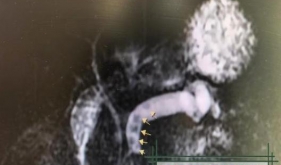

成都市第五人民医院消化内科是集临床、科研、教学为一体的重点学科。共设床位54张,拥有消化内镜中心及消化道动力检测室。共有医生23名,其中主任医师2名,副主任医师3名,主治医师12名,住院医师6名,其中博士生1名,硕士研究生9名,出国访问学者3名。为成都西部地区消化疾病诊断治疗中心,现是成都中医药大学、泸洲医学院、川北医学院、遵义医学院的教学和实习基地。为国家消化病临床研究中心早期胃癌筛查研究协同网络协作中心。消化内科拥有电子胃肠镜、超声内镜、胶囊内镜、胃肠动力检测系统、ERCP室、人工肝、肝脏瞬时弹性成像设备、氩气刀、全自动洗消机、C13和C14...